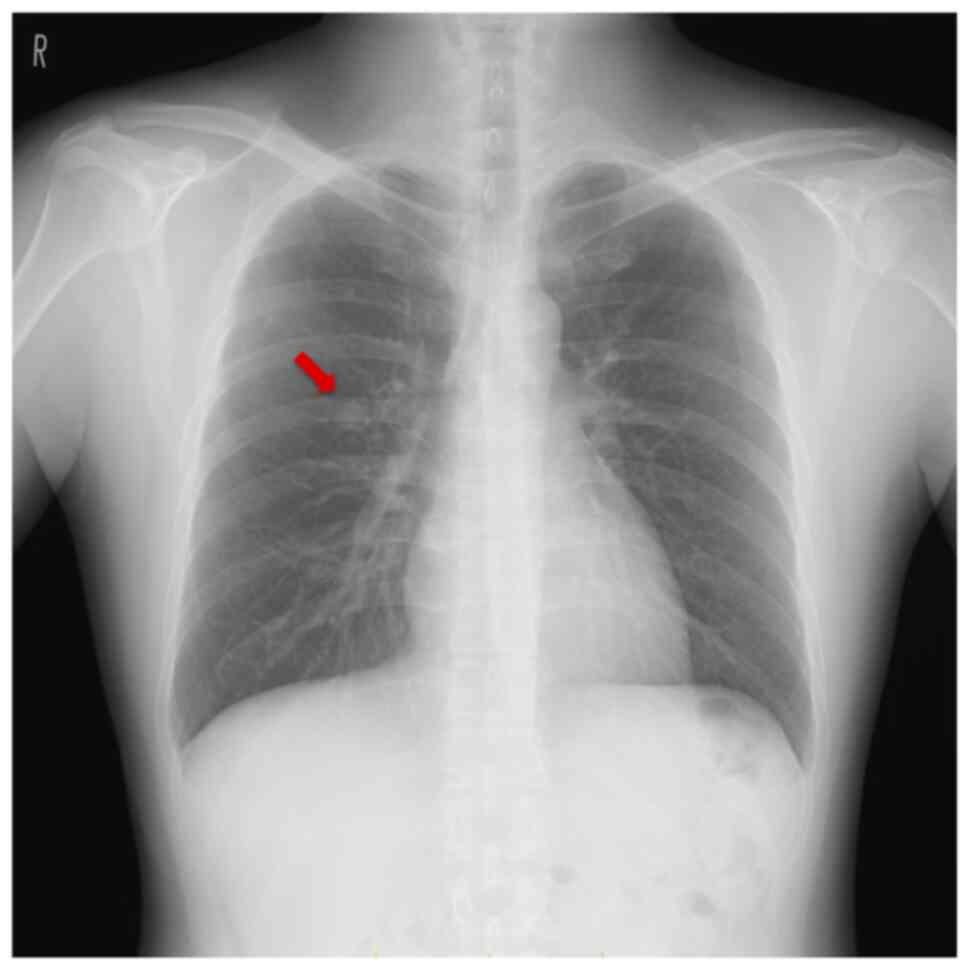

The chest radiograph revealed a smooth-surfaced nodule in the right middle lung field (Fig. 1), and CT revealed a 10-mm smooth-surfaced nodule on the right lung segment 3, which was protruding to B3b with a length of 4.6 mm. After 3 and 6 months, follow-up CTs revealed that the tumor had enlarged to 15 mm, was crawling along the intra-bronchus, and had eventually reached the bifurcation between B3a and B3b (Figs. 2A and B, and 3A and B). Neither enlarged lymph nodes nor metastases were detected on CT. Laboratory examinations revealed no renal (Cre 0.81 mg/dl) or hepatic dysfunction (AST 27 U/l, ALT 29 U/l) and tumor marker levels within the normal ranges, including the carcinoembryonic antigen (1.5 ng/ml), carbohydrate antigen 19-9 (8.0 U/ml), and squamous cell carcinoma antigen (0.8 ng/ml). Only mildly elevated levels of total cholesterol (221 mg/dl) and mild prolongation of prothrombin activation (125%) were observed. Although an intrapulmonary or bronchogenic benign tumor was suspected (e.g., pulmonary sclerosing hemangioma, hamartoma, leiomyoma, and lipoma), malignant diseases such as pulmonary carcinoid tumors could not be completely excluded because of the tumor enlargement. Therefore, we performed a robotic portal right upper lobectomy for tumor resection and diagnosis.

Figure 1

Representative images of the chest radiograph. A smooth surfaced nodule at the right middle lung field (red arrow).

Radiologically, the leiomyoma is located intra- or extratracheally on chest radiographs. On CT, the leiomyoma presents as a smooth-surfaced solitary nodule with homogeneous or heterogeneous enhancement (9). Differential diagnoses for the tracheobronchial type are benign disease (e.g., granulomatous disease, sarcoidosis, amyloidosis, fibroepithelial polyp, and broncholith), infections (e.g., fungal, endobronchial tuberculosis, and hydatid disease), and malignant diseases such as lung cancer and bronchial carcinoid (10). Differential diagnoses of the pulmonary parenchymal type are benign tumors (e.g., hamartoma, pulmonary sclerosing hemangioma, leiomyoma, fibroid tumor, and lipoma), malignant diseases (e.g., lung cancer, metastatic lung tumor, and pulmonary carcinoid), infection (tuberculosis, non-tuberculosis mycobacterial infection, bacterial abscess, and aspergilloma), and pulmonary arteriovenous malformation (11). Because radiographical findings, including CT, are nonspecific with the tracheobronchial and pulmonary parenchymal types, pathological examination via bronchoscopy and surgical resection is necessary to diagnose pulmonary leiomyoma. Regarding the diagnosis of the iceberg growth pattern tumor, malignant diseases such as pulmonary carcinoid and mucocutaneous carcinoma should be considered (2). Our patient had a smooth-surfaced nodule in the right middle lung field on chest radiography, and CT revealed that the tumor had enlarged and crawled to the central bronchus over time. Consequently, we performed a right upper lobectomy for tumor resection and diagnosis.